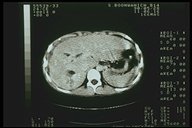

Severe liver injury, multiple laceration over the right lobe are noted from CT scan

Splenic laceration demonstrated by CT scan

Combined severe liver injury and splenic hematoma, intraperitoneal bleeding is also noted